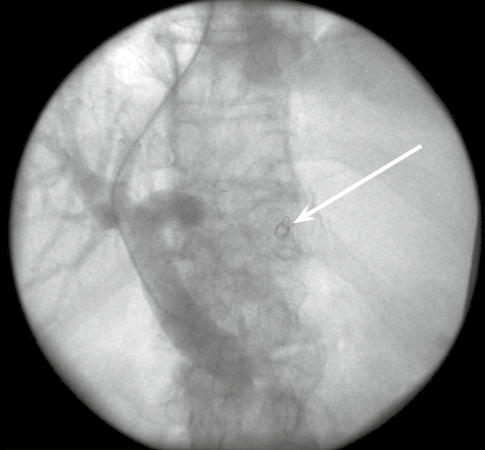

Благоприятный исход операции TIPS/ТИПС с эмболизацией желудочных вен демонстрируется на примере пациента К. 72 лет с циррозом печени вирусной этиологии, варикозным расширением вен пищевода и желудка III ст. (в анамнезе 2 эпизода кровотечения, острый инфаркт миокарда 12 лет назад), постгеморрагической анемией, асцитом, хронической печёночно-клеточной недостаточностью класса С (8 баллов по Child-Turcotte-Pugh), печёночной энцефалопатии I стадии (рис. 4). Спустя 5 лет после операции анализ результатов и эффективности лечения установил отсутствие рецидивов кровотечения, регрессирование варикозного расширения вен пищевода и асцита, отсутствие прогрессирования печёночной недостаточности. На 79-м году жизни пациент К. умер от двусторонней пневмонии, явившейся осложнением ОРВИ.

Рисунок 4. Ангиограмма больного К., 72 г. (контрольная портограмма после выполнения эмболизации спиралями Gianturco левой желудочной вены через сформированный внутрипеченочный канал). Стрелкой указана спираль Gianturco.

Figure 4. Angiogram of patient K., 72 L. (control portogram after Gianturco spiral embolization of the left gastric vein through the formed intrahepatic duct). The arrow indicates the Gianturco spiral